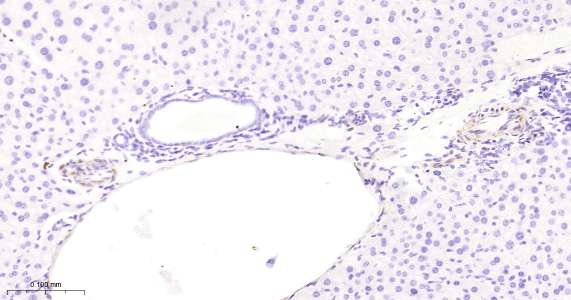

Immunohistochemical analysis of paraffin embedded mouse liver tissue slide using IHC0458M (Mouse Hsp27 IHC Kit).